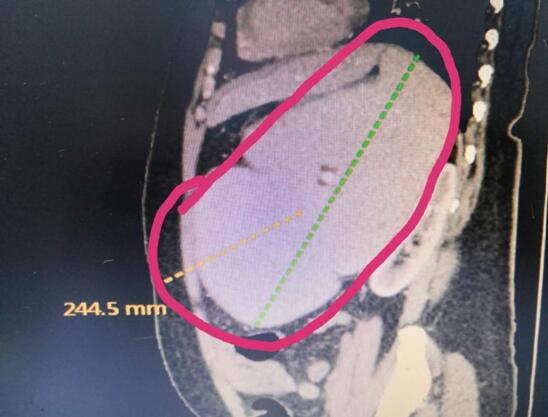

患者B,女,51歲,因牙齦出血1年入院,入院診斷為:乙肝,肝炎后肝硬化,門脈高壓癥,巨脾,脾亢,白細(xì)胞、血小板減少,中度貧血。5年前,曾在外院行介入脾栓塞術(shù),脾臟不僅沒有縮小,反而越來越大,脾下緣已經(jīng)超過腹部正中線、抵達(dá)臍部,就像幾個月“身孕”的婦女,給病人帶來巨大身心負(fù)擔(dān)。

(術(shù)前腹部CT顯示巨脾)